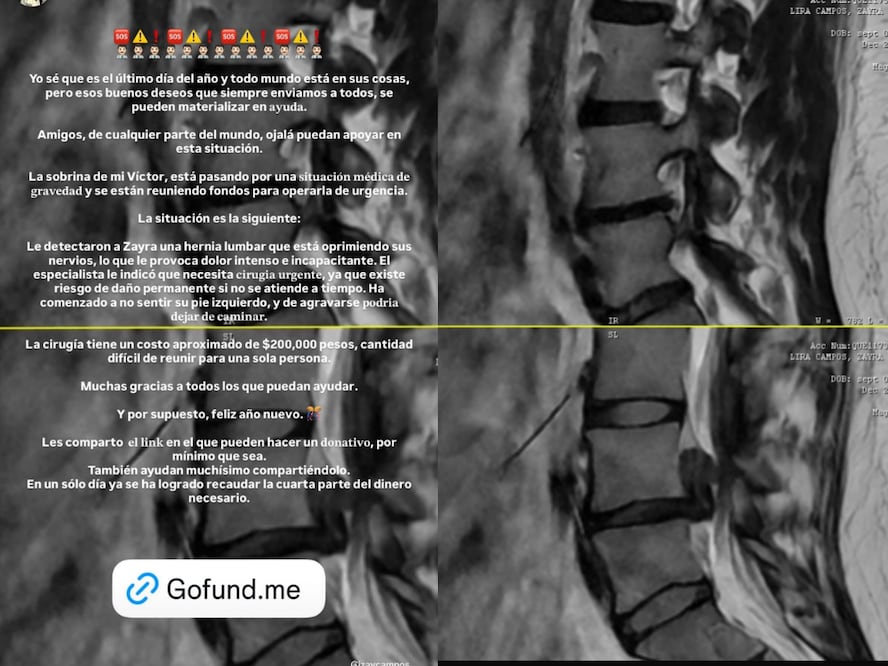

De acuerdo con la información compartida, a la joven le fue diagnosticada una hernia lumbar que comprime los nervios, lo que le genera dolor intenso e incapacitante. El especialista que la atiende indicó la necesidad de una intervención quirúrgica inmediata, debido al riesgo de daño permanente.

Actualmente, "Zayra ha comenzado a no sentir su pie izquierdo, y de agravarse podría dejar de caminar", compartió Rabell.